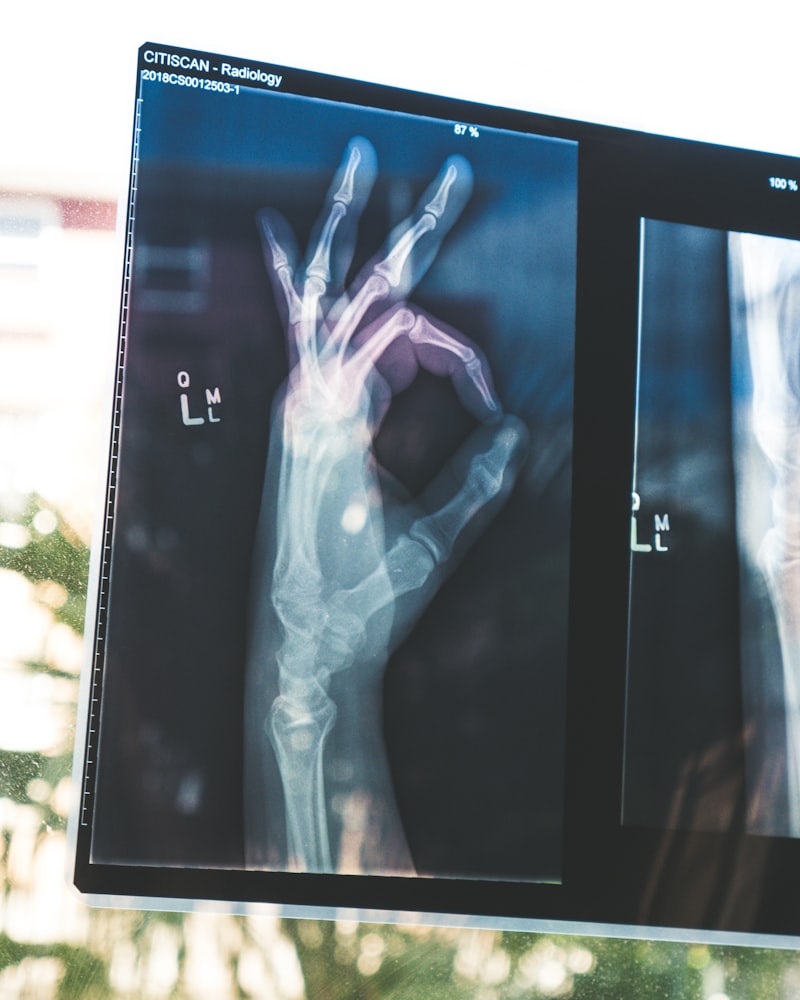

Diagnostics

On-site X-ray and laboratory services for accurate diagnosis.